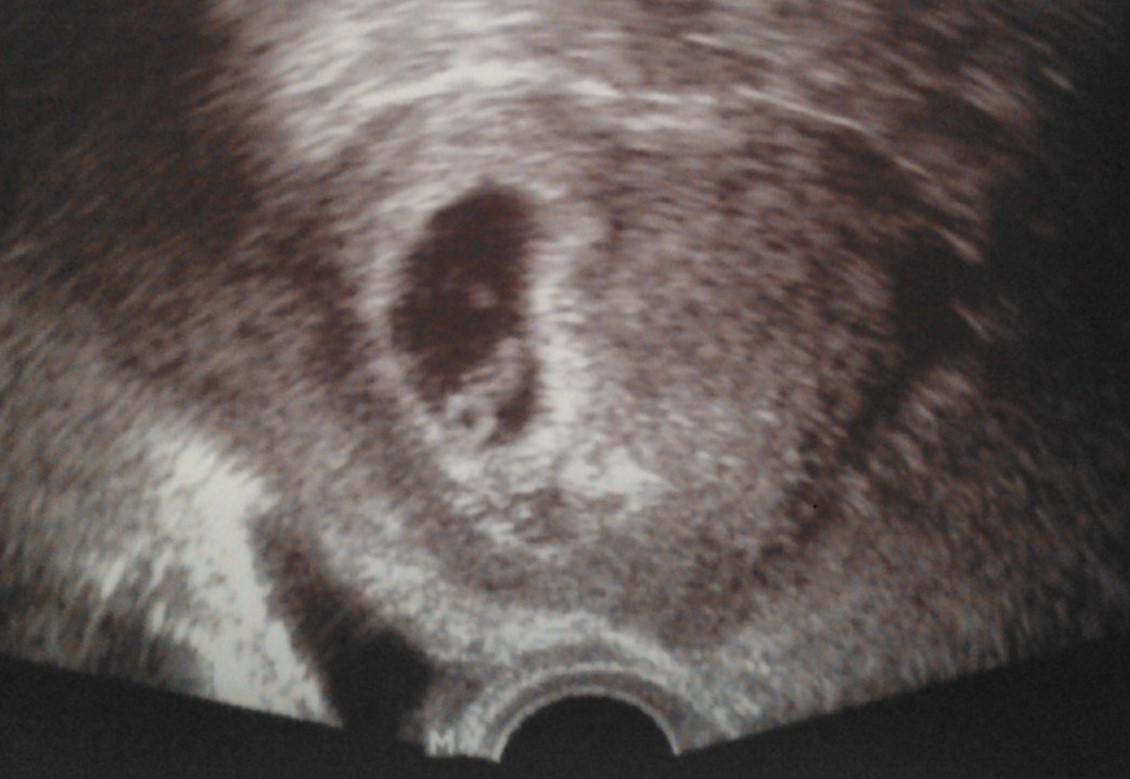

@dievca92 vobec nestresuj, len si isla skor ako bolo treba k Dr...Ja som bola prvykrat u Dr. v 6tt.a bolo videt vacok a za dalsie 3 tyzdne uz aj placentu a babätko malicke - prikladam foto (9tt)...Takze neboj, dockas sa, len treba trpezlivost...Tes sa na dalsiu kontrolu a hlavne bud v klude 😉